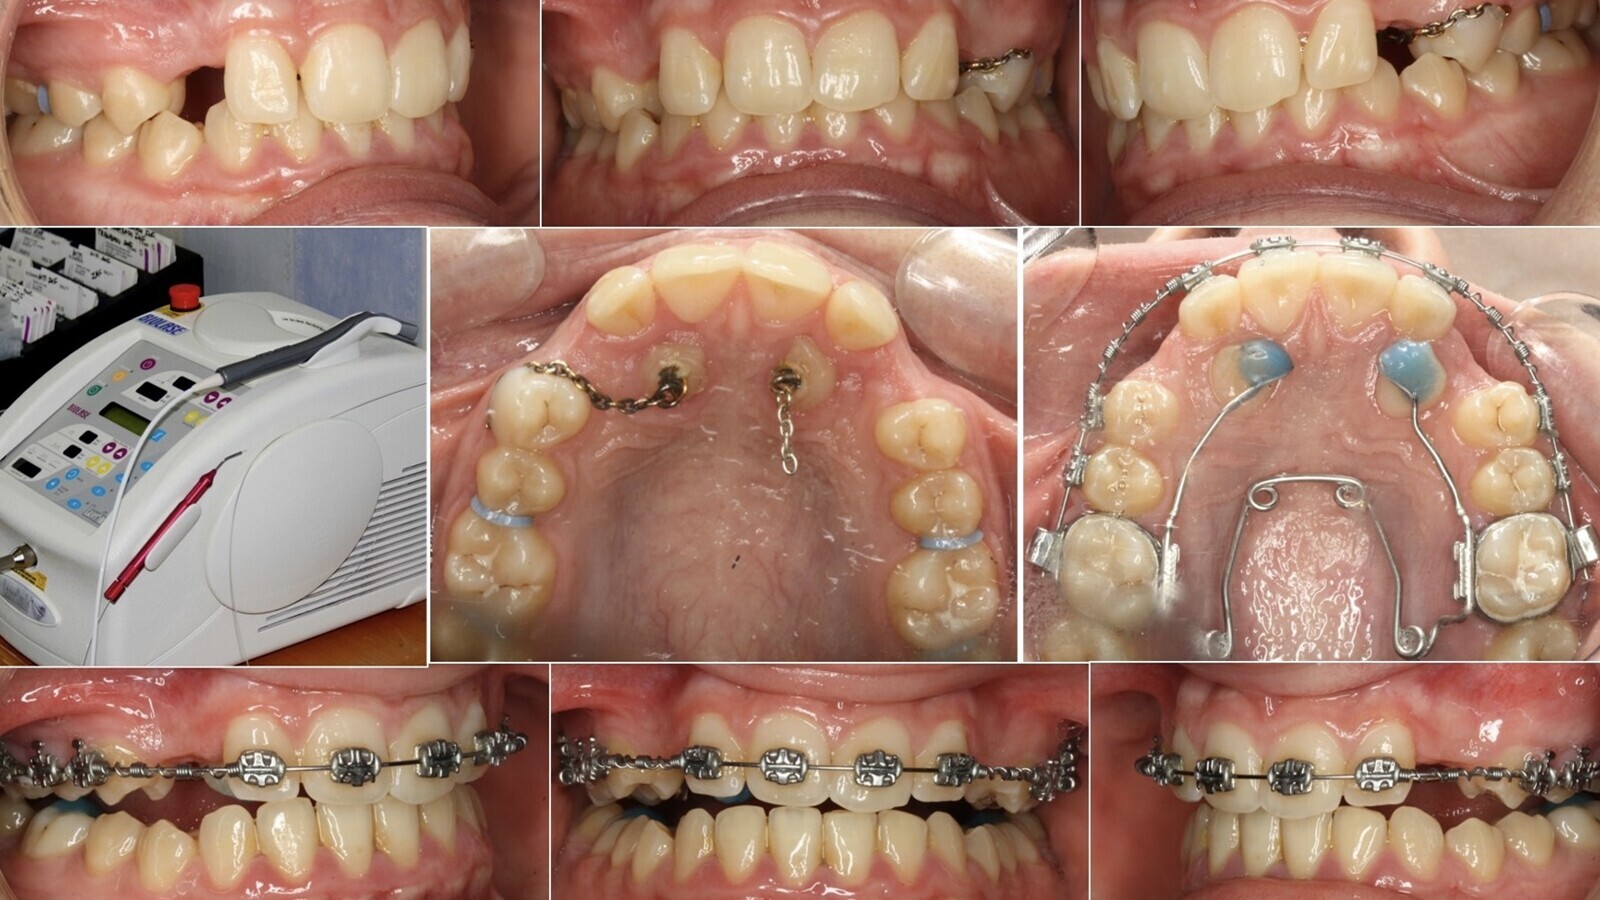

Los autores de este artículo clínico describen el protocolo que utilizan en el Servicio de Investigación en Ortodoncia – Unidad Dental del Sueño de la Universidad de Santiago para evaluar la posibilidad de bajar o no un canino incluido/retenido en el paladar.

La retención/inclusión palatina de los caninos superiores es un problema frecuente en ortodoncia, que afecta hasta un 2% de la población general y que muchos profesionales asocian a dos palabras: incertidumbre y excesivo tiempo de tratamiento.

El propósito de este sencillo artículo clínico es describir el protocolo que utilizamos para valorar la viabilidad de bajar o no un canino incluido/retenido en el paladar.

Gran parte de los problemas de los caninos derivan de dos hechos mecánicos: el largo camino que ha de recorrer desde la parte apical de la fosa canina, a los lados de la apertura piriforme, hasta su posición final en la arcada y el ser uno de los últimos dientes en hacer erupción/emergencia en el maxilar (figura 1).

Al igual que los peregrinos que van a Santiago de Compostela necesitan que su camino esté despejado, el canino superior necesita un camino de emergencia, una guía, constituida por la cara distal de la raíz del incisivo lateral; cuando el tamaño o morfología de esta raíz no es la adecuada, el canino se pierde y escoge la vereda palatina (figura 2).

En otras ocasiones, pequeños obstáculos en el camino, como la retención prolongada de un canino temporal, pueden desviar al canino de su trayecto eruptivo normal; esta situación es mucho más frecuente de lo que podría pensarse (figura 3). En nuestra experiencia, los casos más complejos y de sombrío pronóstico se asocian a malformaciones radiculares (raíces en forma de gancho, raíces dilaceradas, raíces dobles). Para complicar más el tema, los caninos pueden producir la lesión o destrucción parcial de los dientes vecinos y, desgraciadamente, no es infrecuente ver en la tracción ortodóncico-quirúrgica de un canino una marcada reabsorción radicular externa de los dientes vecinos, con especial frecuencia y énfasis en el incisivo lateral superior.

A todas estas complicaciones hay que sumar el tiempo y la difícil comprensión del paciente del alcance del tratamiento. Es extremadamente raro poder resolver un caso de canino/s incluido/s de moderada dificultad en menos de 30 meses. Cuando este problema se acompaña de otros que se pueden resolver al mismo tiempo (marcado apiñamiento e irregularidad dentaria, compresión maxilar, mordida cruzada), aún tenemos algo que ganar si las cosas se complican, pero cuando la inclusión canina es el único objetivo terapéutico, el profesional se lo ha de pensar y repensar varias veces; la ley del todo o nada funciona mal en nuestra especialidad.

Las tablas pronóstico que presentamos son una aproximación clínica y subjetiva al problema; no derivan de una investigación rigurosa, sino de ese feeling que los clínicos vamos atesorando en nuestra mente tras acertar algunas veces y fracasar muchas. Ayudarán a que el clínico experimentado, curtido por los años, mande extraer menos caninos incluidos, al menos los de mejor pronóstico, y a que el novato no se meta en misiones imposibles que acaban en un desagradable conflicto con el paciente tras robar muchas horas de sueño al profesional. O cruzamos el río o no lo cruzamos, pero lo peor es quedarse en mitad de la corriente y que ésta nos arrastre hacia la catarata. Ni que decir tiene que el CBCT/TAC es crucial en el pronóstico del problema, es el arma diagnóstica definitiva. Hay que pensar siempre en los tres planos del espacio y entender que la mayoría de los caninos se mueven en un espacio cónico cuyo vértice se localiza en la parte más apical de la fosa canina; cuando el canino se sale de este espacio cónico virtual hay que ir pensando en darlo por perdido (figura 4).

1. Meter el dedo para no meter la pata. La palpación palatina de los caninos nos orienta hacia su posición. El CBCT/TAC es el arma diagnóstica definitiva.

2. No tratar de bajar caninos imposibles; el incisivo lateral superior y el prestigio de su clínica se lo agradecerá.

3. Siempre realizar primero tracción vertical y después horizontal. La tracción horizontal sostenida crea los inespecíficos “caninos anquilosados” al acostar al canino sobre la cortical palatina (figura 12). Una tracción horizontal inadecuada a una distancia considerable es garantía de fracaso. En estos casos, el canino se horizontaliza y es inviable su colocación correcta en arcada.

4. Utilizar siempre tracción vertical inicial (figura 13).

5. Saber en qué posición exacta está el canino durante todo el proceso de tracción ortodóncica.

6. Los Microimplantes son un excelente anclaje, seguro, indoloro, confortable y económico, para la tracción ortodóncica inicial de los caninos (figuras 14, 15 y 16).

7. Muchos caninos están en una situación inframucosa o recubiertos por una lámina fina de hueso; evitar amplios cortes y colgajos palatinos. Ante la duda, realizar tunelización o colgajo de reposición apical para evitar futuras recesiones gingivales o dehiscencias.

8. Una vez que se ha conseguido colocar en arcada la corona del canino, hay que realizar el trabajo hercúleo de dar torsión negativa a su raíz. Para ello recomendamos el uso de resortes en aleaciones de TMA o Gummetal con arcos gruesos (mínimo de 0.019x25”) y hacer entender al paciente la necesidad de tiempo para que el movimiento de torsión radicular negativa se produzca (figuras 17 y 18).

9. En nuestra experiencia, las Microosteoperforaciones en el hueso enfrentado al movimiento dentario es una excelente opción para acelerar el movimiento dentario ortodóncico y acortar la duración del tratamiento. Estas Microosteoperforaciones, realizadas con una fresa de tugsteno a 2-4-7 mm de profundidad estimulan el RAP (rapid acelerated phenomen) y el reclutamiento de células progenitoras y osteoclastos (figuras 19 y 20).

10. Antes de afrontar la ardua travesía de traer un canino incluido a su posición en la arcada hay que valorar el estado general de la boca del paciente, es decir, si resistirá el periodonto toda la biomecánica que el caso demanda, la maloclusión general del paciente y, muy importante, su discrepancia óseodentaria y/o la necesidad de realizar extracciones terapéuticas (en este caso siempre optamos por la extracción del canino en lugar del premolar vecino). Las placas removibles con resortes pueden ser de gran ayuda para dar torsión radicular negativa final a los caninos traccionados (figura 21).

La herramienta diagnóstica definitiva para evaluar la posibilidad de bajar o no un canino incluido/retenido en el paladar es el CBCT/TAC. Las tablas diagnósticas que ofrecemos complementan una aproximación clínica al problema, que ayudarán al ortodoncista a evitar extracciones innecesarias y a mejorar el diagnóstico de estos casos.